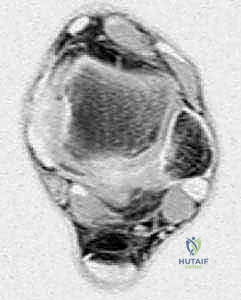

Advanced Imaging Modalities

Magnetic Resonance Imaging (MRI) with and without intravenous gadolinium contrast is the gold standard for local staging. MRI delineates the intra- and extra-compartmental extent of the tumor, its relationship to the intermuscular septa, and its proximity to the superficial femoral artery and femoral nerve. T1-weighted images are excellent for assessing marrow infiltration if bone involvement is suspected, while fluid-sensitive sequences (T2-weighted fat-suppressed or STIR) highlight peritumoral edema, which often dictates the extent of the reactive zone and the required surgical margin.